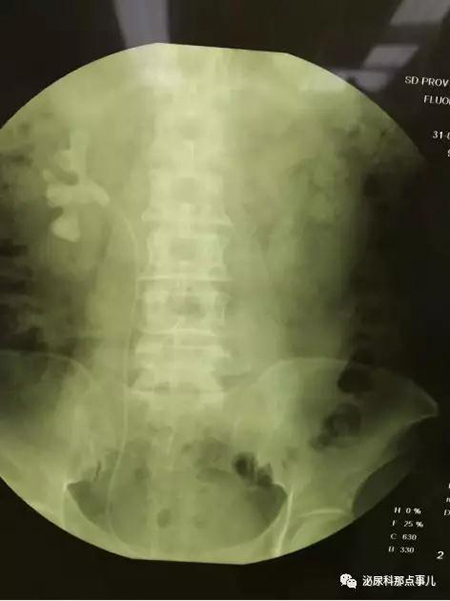

术后KUB